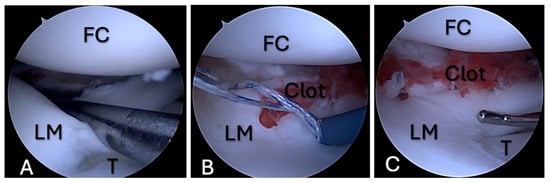

The quantity of fibrin clot pieces required depended upon the extent of the meniscal tear, as was typical with the sutures. Figure 2, Figure 3 and Figure 4 present several cases of meniscus repair augmented with FC.

Figure 2. FC application during meniscal repair, case 1. (A)—A bucket-handle tear of the lateral meniscus; (B)—an FC between the edges of the meniscus tear, with a type of suture that is placed across the tear; (C)—an FC between the tear edges that is fixed with sutures. FC—femoral condyle; LM—lateral meniscus; T—tibia.